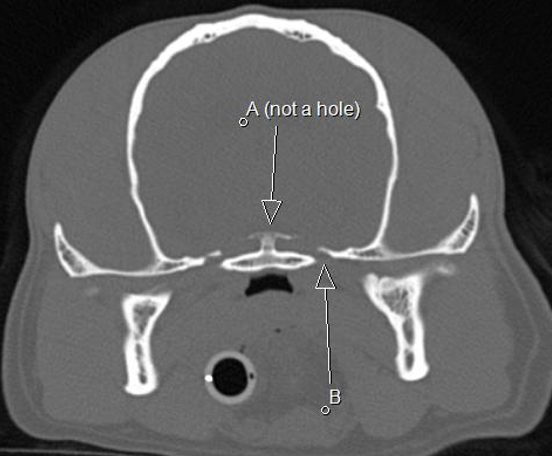

A dorsum sella B oval foramen